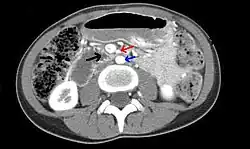

| Abdominal and pelvic computed tomography scan showing duodenal compression (black arrow) by the superior mesenteric artery (red arrow) and the abdominal aorta (blue arrow). | |

Diagnosis is very difficult, and usually one of exclusion. SMA syndrome is thus considered only after patients have undergone an extensive evaluation of their gastrointestinal tract including upper endoscopy, and evaluation for various malabsorptive, ulcerative and inflammatory intestinal conditions with a higher diagnostic frequency. Diagnosis may follow X-ray examination revealing duodenal dilation followed by abrupt constriction proximal to the overlying SMA, as well as a delay in transit of four to six hours through the gastroduodenal region. Standard diagnostic exams include abdominal and pelvic computed tomography (CT) scan with oral and IV contrast, upper gastrointestinal series (UGI), and, for equivocal cases, hypotonic duodenography. In addition, vascular imaging studies such as ultrasound and contrast angiography may be used to indicate increased bloodflow velocity through the SMA or a narrowed SMA angle.[14][15]